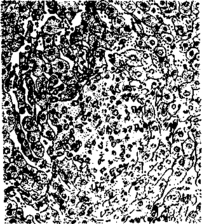

При гистологическом исследовании в селезенке находят диффузную или очаговую крупноклеточную гиперплазию с некробиотическими изменениями в очагах пролиферации. В печени узелки могут быть двух типов. Одни из них - простые неспецифические токсические некрозы печеночных клеток, другие - гранулемы, расположенные интралобулярно. Они известны под названием паратифозных узелков. Простые некрозы - результат сильного токсического действия на печеночные клетки и эндотелий сосудов продуктов обмена бактерий, представляют собой коагуляционно-некротические очажки. Вокруг них реактивная зона отсутствует или можно наблюдать набухание и пролиферацию клеток ретикуло-эндотелия.

Некротический фокус в печени теленка при сальмонеллезе

Гранулемы (паратифозные узелки) имеют вид очажков размножающихся ретикулоэндотелиальных элементов, расположенных по ходу капилляров. Клетки гранулем со светлыми крупными ядрами обладают способностью к фагоцитозу. Кроме печени и селезенки паратифозные узелки отмечают также в почках, лимфатических узлах, костном мозге. В печени и реже в других органах можно наблюдать образование очаговых эндофлебитов, но они не патогномоничны для сальмонеллеза.